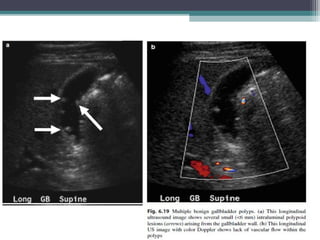

GALL BLADDER POLYP

Lesions that project from the gall bladder wall into the gallbladder lumen are

called gallbladder polyps .

They include neoplasms such as adenomas or adenocarcinomas and nonneoplastic

lesions such as cholesterol polyps (most common), infl ammatory polyps, and

hyperplastic polyps.

Many lesions identified as polyps on USG prove to be small gallstones upon

cholecystectomy . Gallstones that are adherent to the gallbladder wall and do not

show clear shadowing may mimic polyps .

Imaging

 USG:

• Single or multiple, immobile, nonshadowing lesions arising from the gallbladder

wall.

• Ultrasonography is unable to reliably differentiate benign from malignant

polyps . Multiplicity and polyps smaller than 10 mm are more suggestive of

benignity.

• Gallbladder polyps are differentiated from gallstones by their lack of shadowing

and mobility.